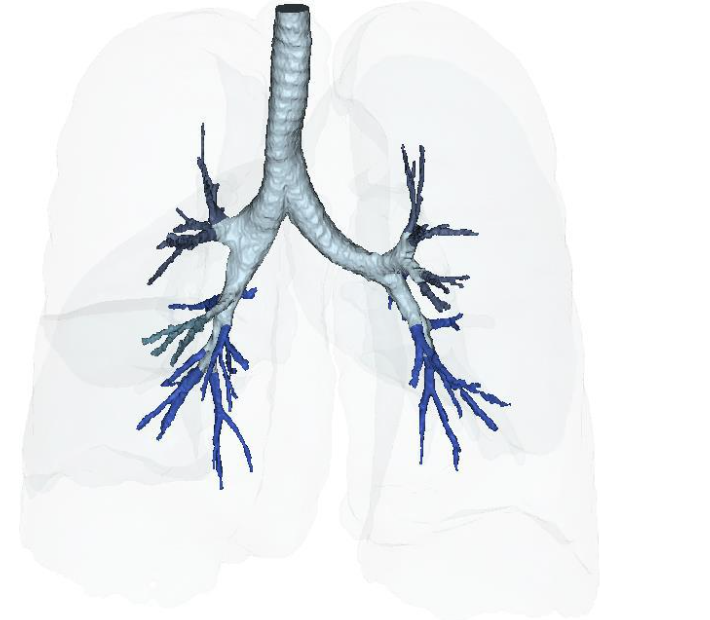

Figure 15A: Vascular Perfusion Changes Pre-treatment of Long COVID-19 lung vascular changes. Figure 15B: Post IV deployment cSVF therapy in Long COVID-19 clinical trial NCT04326036 at 6 months. Figure 16A: Restoration of the near terminal Tracheobronchial tree, pre-treatment showing blunting and loss of distal bronchioles. Figure 16B: Post-treatment IV cSVF with elongation of distal bronchiolar tree at six months. NOTE: With this post-treatment changes with cSVF was an accompanying reduction in airway resistance and pressures within the lung parenchyma. Higher pressures in pre-treatment image were located in the Upper lobes (less efficient and higher pressures in pre-treatment), whereas the shift from upper to lower lung parenchyma accompanied improve vascular supply and perfusion, and patients no longer experienced difficulties in inhalation capabilities.